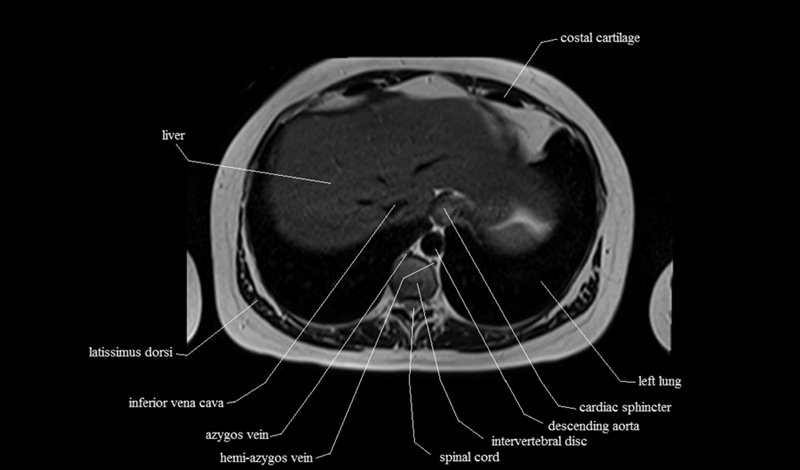

MRI Axial Cross Sectional Anatomy of Chest

This MRI chest (thorax) axial cross sectional anatomy tool is absolutely free to use. Use the mouse scroll wheel to move the images up and down, or alternatively, use the tiny arrows (→) on both sides of the image to navigate through the images. For a more detailed view, double-click the image to view it in full screen, and use the menu in the top right-hand corner to view individual slides or play them in a loop.